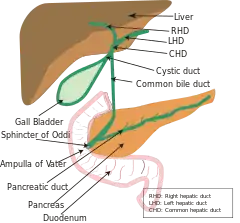

A diagram of the biliary system. Note that the ampulla of Vater is behind the major duodenal papilla. | |

The ampulla of Vater, hepatopancreatic ampulla or hepatopancreatic duct is the common duct that is usually formed by a union of the common bile duct and the pancreatic duct within the wall of the duodenum. This common duct usually features a dilation ("ampulla"). The common duct then opens medially into the descending part of the duodenum at the major duodenal papilla. The common duct usually measures 2-10mm in length.[1]

The ampulla of Vater is an important landmark halfway along the second part of the duodenum marking the transition from foregut to midgut.

Various smooth muscle sphincters regulate the flow of bile and pancreatic juice through the ampulla: the sphincter of the pancreatic duct, the sphincter of the bile duct, and the sphincter of Oddi.[3]

The common bile duct and pancreatic duct may sometimes unite outside the duodenal wall, creating an unusually long common duct. The two ducts may also drain into the duodenum separately, or may fuse yet retain their separate lumens separated by a septum.[1]